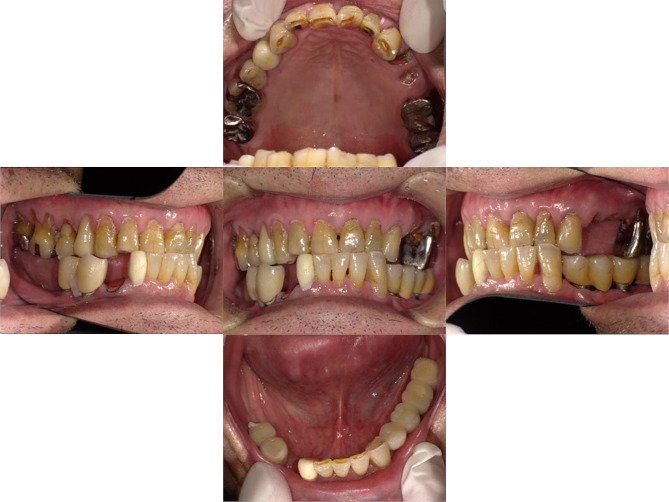

Case presentation: An 81-year-old male patient with Parkinson's disease presented to our outpatient clinic with bruxism and crossbites. FIPs, with five Brånemark system implants, were placed in the bilateral lower molars. The FIP was replaced with an IOD with two locator attachments to create an oral environment that was easier for caregivers to clean and allow easy recovery of masticatory function if residual teeth were fractured in the care environment. As his systemic condition deteriorated, treatment was changed from outpatient to in-home visits. During dental care visits, professional oral cleaning and denture repair were continued, and good nutritional status was maintained. However, the patient developed cholecystitis and was hospitalized. During hospitalization, gastrostomy was performed because he developed aspiration pneumonia. After discharge from the hospital, the patient remained in bed all day and could not wear an IOD, resulting in buccal mucosa ulceration due to abrasion of the locator abutment. We decided to replace the abutment with cover screws; however, not all the implants could sleep submucosally. Although regular oral cleaning was resumed, new ulcers developed even when cover screws were installed. Additionally, swelling and drainage were observed at the peri-implant mucosal site where peri-implantitis had once occurred during an outpatient visit. The patient was readmitted to the hospital for a urinary tract infection, and subsequent visits were abandoned.